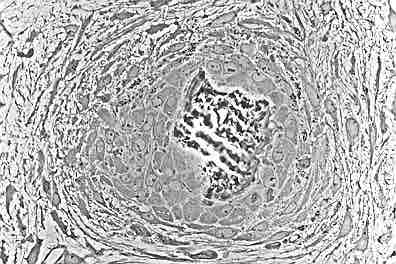

This figure shows osteoblasts creating rudimentary bone tissue.

This figure shows osteoblasts creating rudimentary bone tissue. The osteoblasts are seen lining up on the surface, which increases their size. As growth continues, trabeculae become interconnected and woven bone is formed.